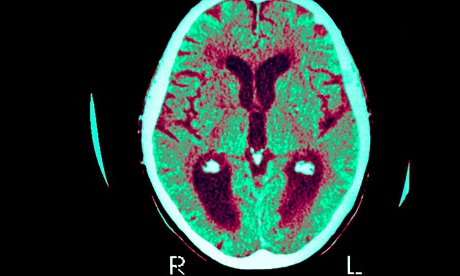

Blood test breakthrough in search for Alzheimer’s cure

alz